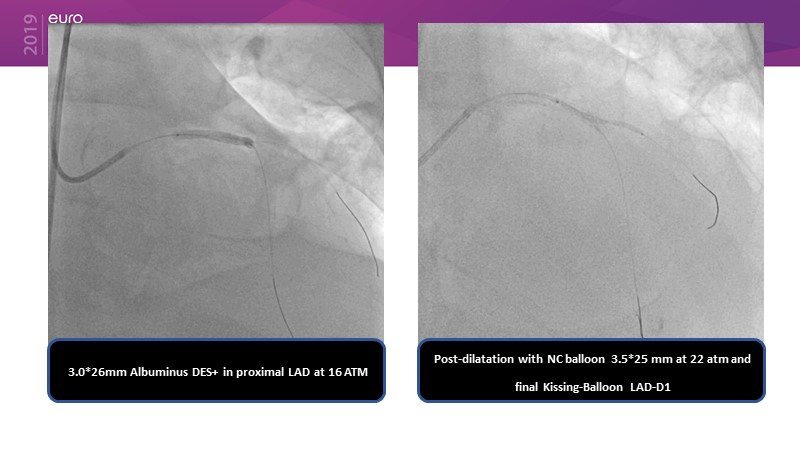

Ability to treat diabetic patients: DES + DCB strategy

Consult this session to get insights about the need for a dedicated drug eluting stent (DES), as well as the benefits of a DES+DCB strategy, for diabetes mellitus (DM) and acute MI (AMI) patients.

- To understand and learn benefits of DES+DCB strategy to provide uniform and homogenous drug delivery in patients with diabetes mellitus and acute MI